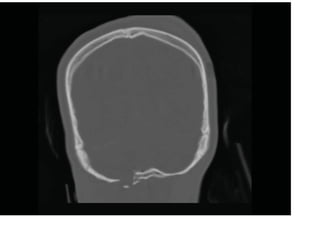

Fenêtres osseuses avec balle logée

Les données du scanner peuvent

être reformatées dans le plan

coronal pour évaluer les fractures

du calvaire.